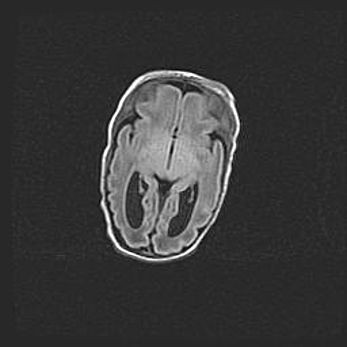

Множественные кисты обоих полушарий головного мозга, наибольшая из них в правой затылочной области. Ассиметричная атрофическая гидроцефалия.

Возраст: 7 месяцев

Вес: 5660 г

Пол: мужской

Окружность головы: 41,5 см

Срок гестации: 28-29 недель

Кисты головного мозга развиваются в результате многоочаговых некрозов вещества мозга и возникают вследствие перенесенной перинатальной инфекции, менингитов, энцефалитов, асфиксии, родовой травмы, расстройств мозгового кровообращения различного генеза. Образованию кист в веществе головного мозга плодов и новорожденных способствуют такие факторы, как высокое содержание в нем воды, недостаточная (или отсутствие) миелинизация и слабая астроглиальная реакция на повреждение.

Кисты могут сочетаться с гидроцефалией и другими поражениями головного мозга.